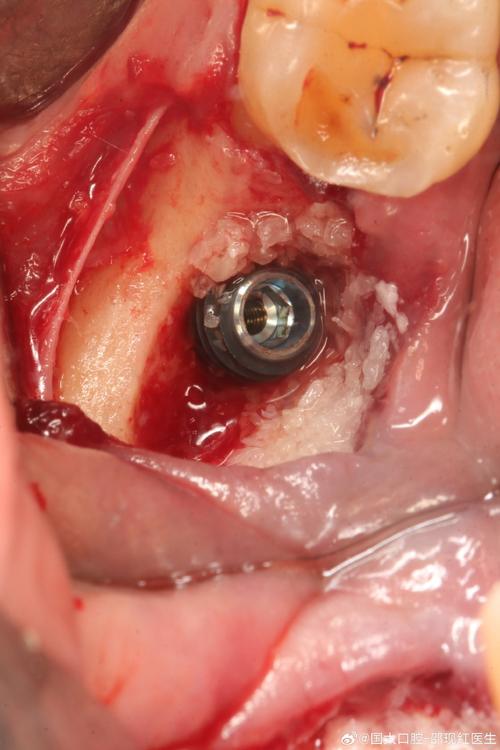

- 植骨手术: 在需要种植的区域进行骨增量。

- 种植体植入: 如果骨条件成熟,即可进行种植手术,将种植体(人工牙根)植入新生骨中。